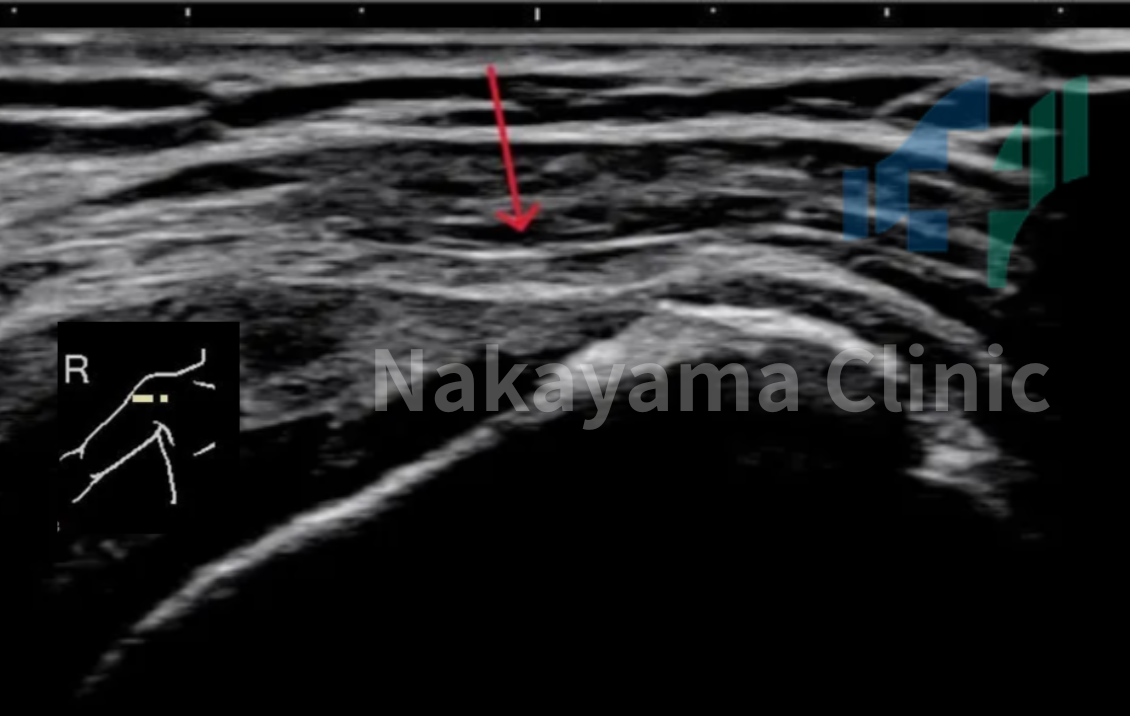

🔍 エコー・MRIを用いた「正確な診断」

「五十肩なのか?」「腱板断裂なのか?」を見極めるために、当院では高性能な超音波(エコー)検査やMRI検査を行っています。

超音波検査は、MRIと同じくらい高い精度で腱板断裂を発見できるという論文データもあり [3]、被ばくの心配もなく、診察室ですぐに肩の内部の状態を確認することができます👀✨